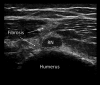

Neuromuscular ultrasound (NMUS) is becoming a standard element in the evaluation of peripheral nerve and muscle disease. When obtained simultaneously to electrodiagnostic studies, it provides dynamic, structural information that can refine a diagnosis or identify a structural etiology. NMUS can improve patient care for those with mononeuropathies, polyneuropathy, motor neuron disease and muscle disorders. In this article, we present a practical guide to the basics of NMUS and its clinical application. Basic ultrasound physics, scanning techniques and clinical applications are reviewed, along with current challenges.